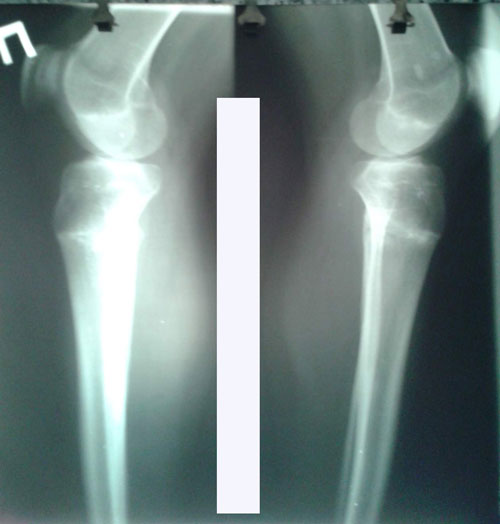

РЕНТГЕН ДО ОПЕРАЦИИ